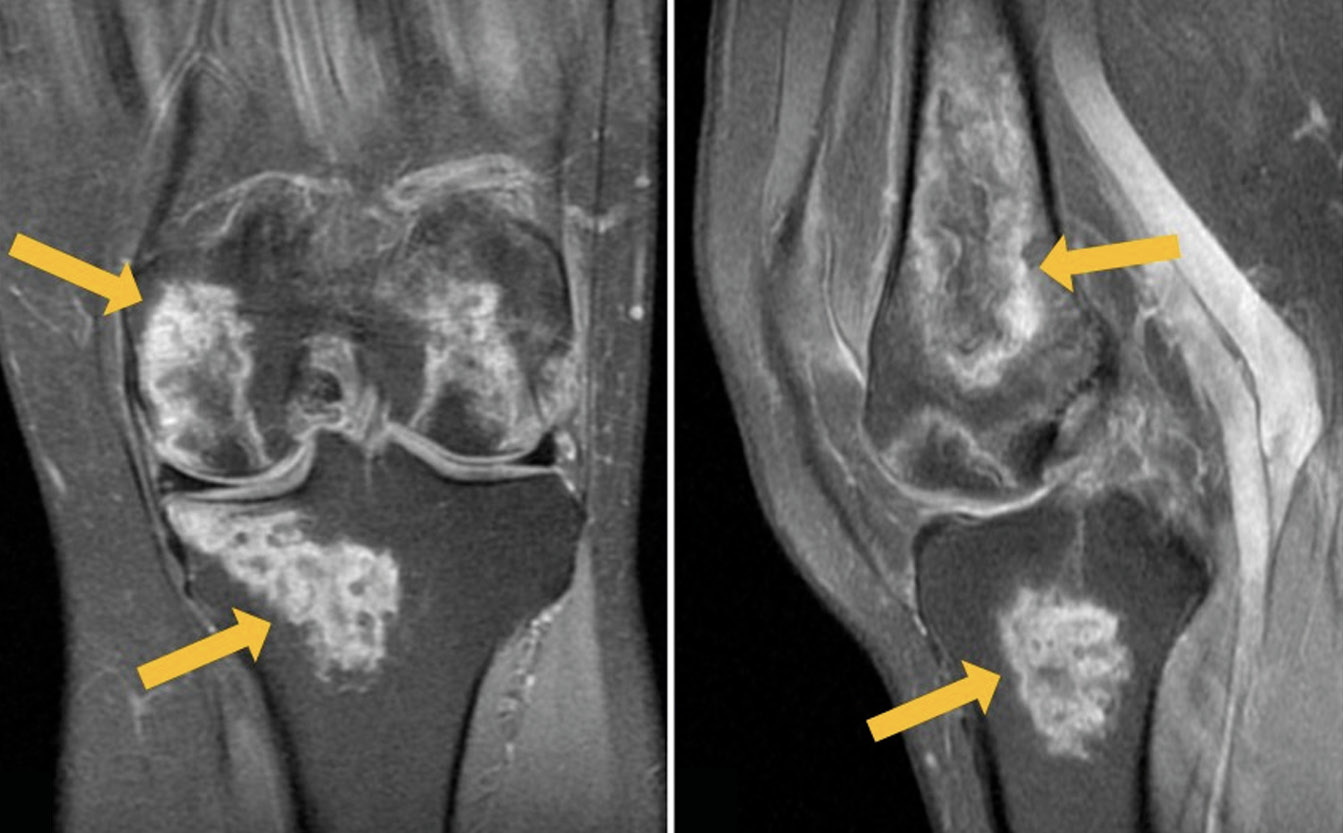

We present a clinical case of a 54-year-old patient hospitalized for novel coronavirus infection with complaints of severe pain in both knees 2 weeks after the disease onset. Magnetic resonance imaging revealed pronounced changes in both knees, corresponding to avascular necrosis. The results of conservative therapy, including non-steroidal anti-inflammatory drugs and bisphosphonate bone resorption inhibitors, produced a pronounced positive result. At follow-up examination 3 months later, there was no pain, but the knee joints still had slight restrictions of movement. Magnetic resonance imaging showed a significant decrease in the previously detected changes.